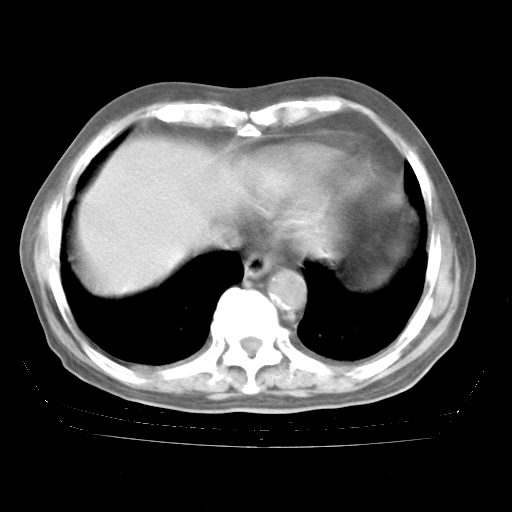

4月28日肺部CT

个人阅读4.14日肺部CT平扫:纵隔窗无异常,但肺窗示:双下肺内、后基底段有片絮状侵润影,部位以后基底段为著,以间质改变为主,呈急性肺泡炎征像,和首次住院影像学有相似之处。仅是个人读片,明日请相关专家再读片哈。其它建议同上。